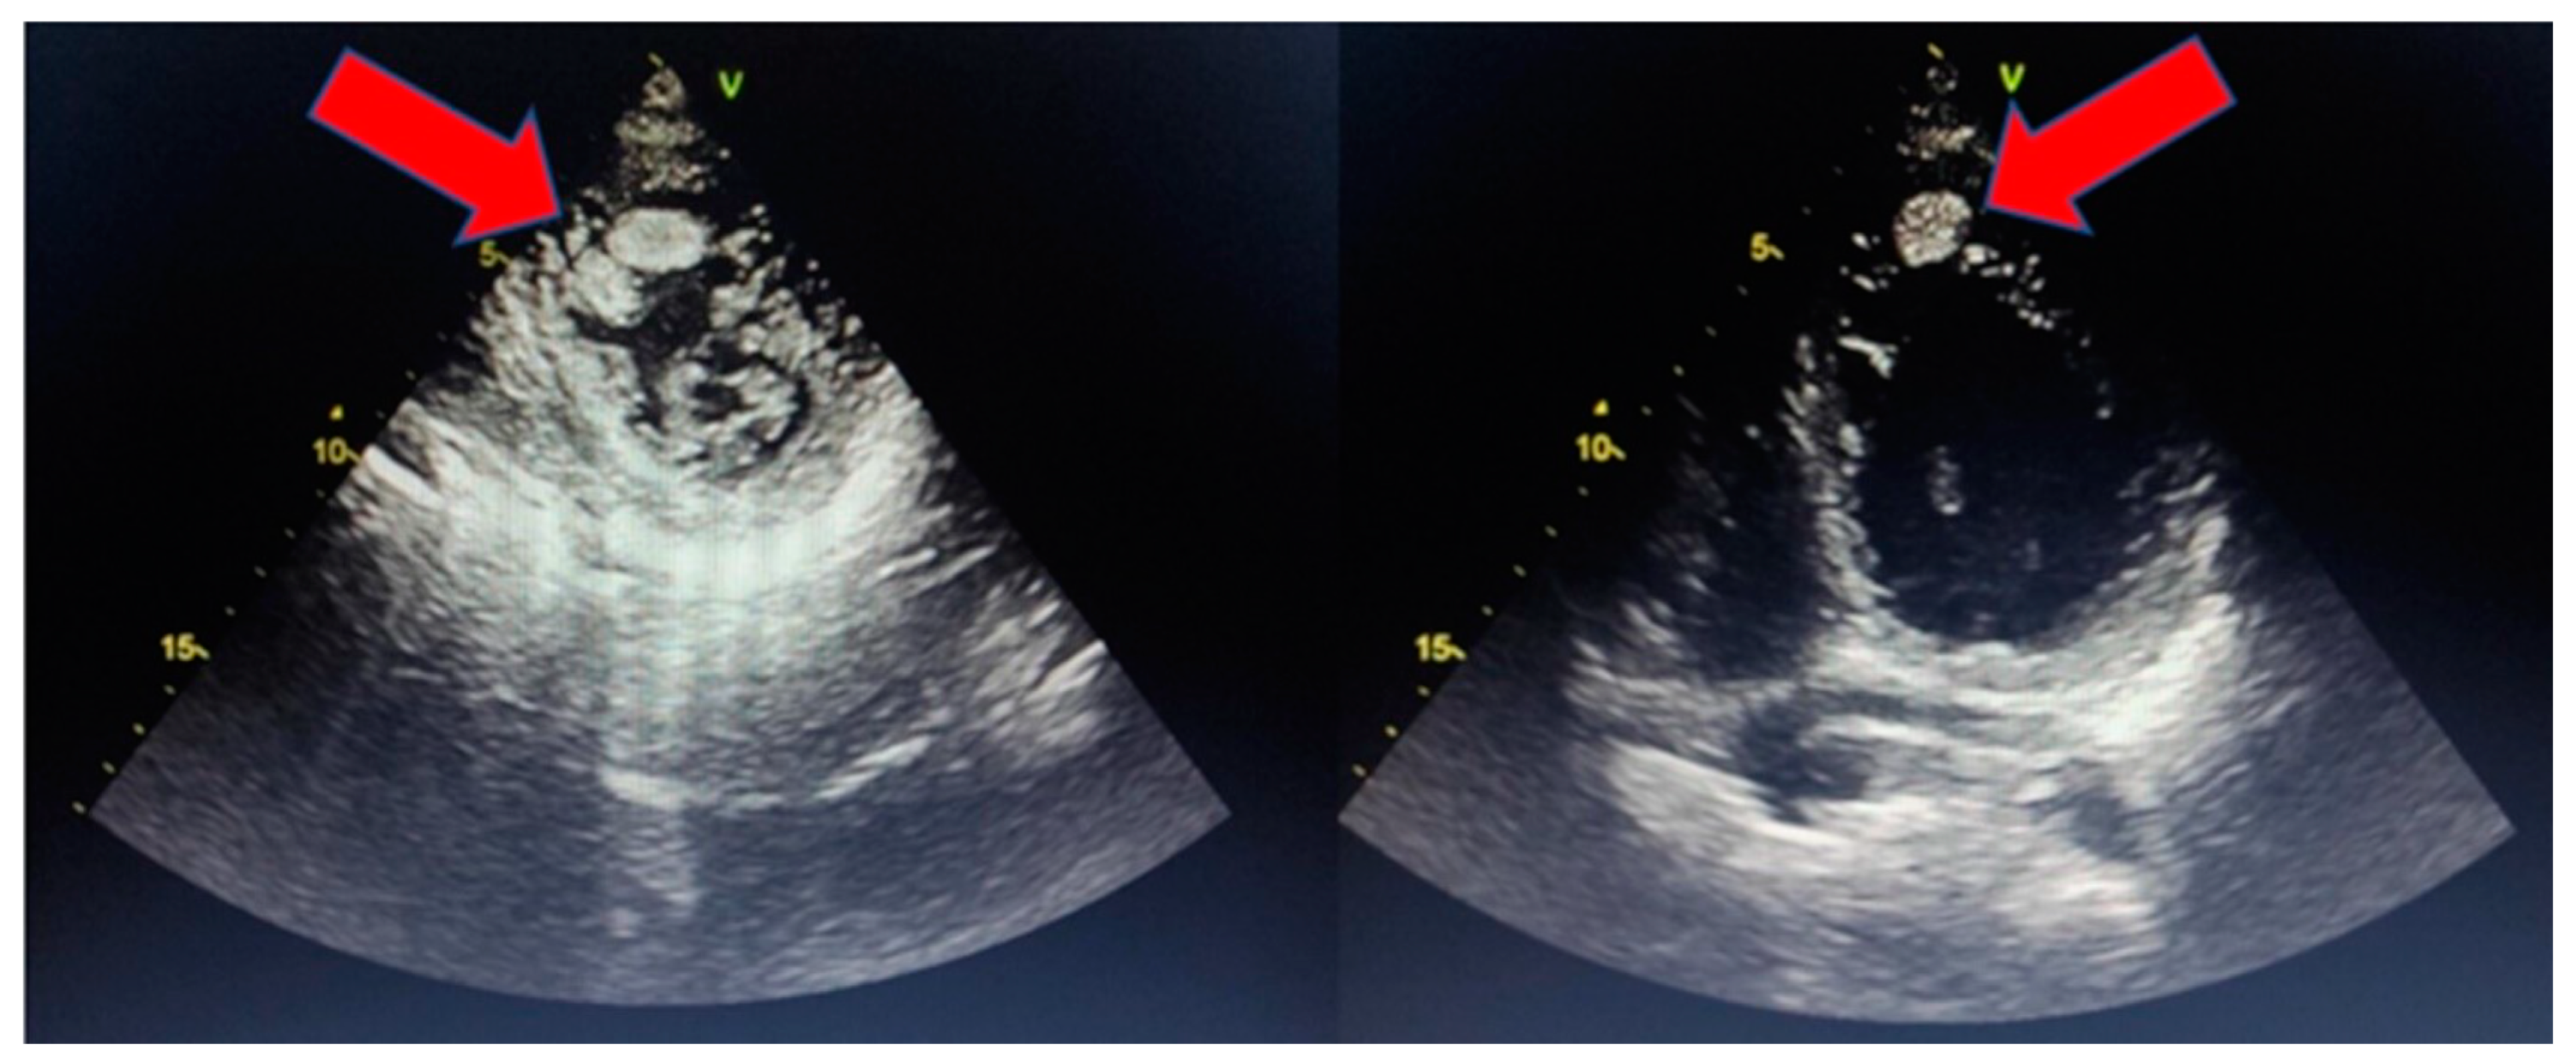

5. Imaging